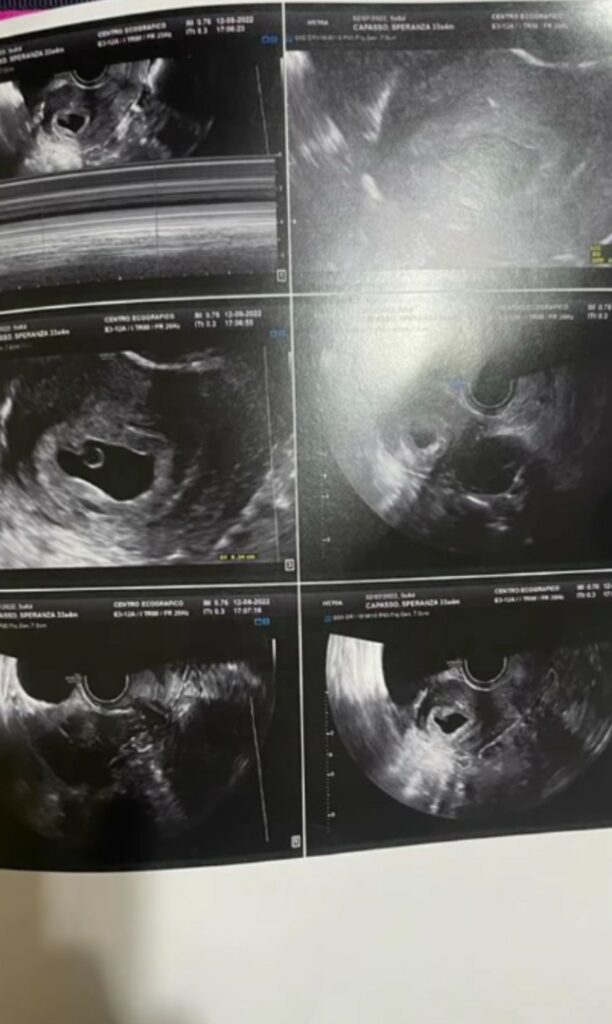

A Temptation Island la loro storia aveva fatto discutere, soprattutto per il tradimento alla luce del sole di lui con una single, Nunzia. Del resto Alberto Maritato era parso non proprio cristallino nei suoi comportamenti anche prima di entrare al reality di Maria De Filippi, almeno così raccontava la fidanzata. I due in Sardegna si erano lasciati, il pubblico era rimasto colpito dalla facilità con cui Speranza Capasso paresse accettare di essere vittima. Adesso però sembrerebbe tutto alle spalle. La 35enne nata ad Avellino che vive a Brusciano, in provincia di Napoli, e lavora in uno dei tre ristoranti Columbus di proprietà del compagno è incinta. Lo annuncia sul social.

“Trovare le parole giuste per spiegare tutto ciò è davvero difficile…non riusciamo più a trattenere questa gioia immensa e siamo qui ad annunciarvi che presto saremo in tre - confessa ai follower su Instagram la Capasso - La paura era ed è ancora tanta, ma l’istinto di condividere con voi questa gioia immensa ha prevalso su tutto…”.